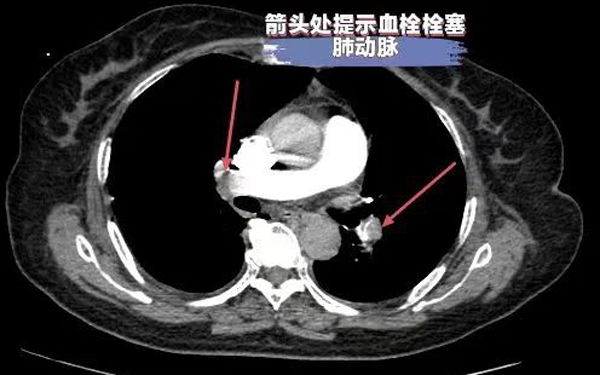

据了解,邓某,因“反复呼吸困难10余天”于外院治疗,效果不佳,症状逐渐加重,辗转多家医院来到我院,入院后患者生命体征不稳定,血压在70/40mmHg左右,心率120次/分左右,面罩吸氧状态下氧饱和度82%,D二聚体明显升高,高度怀疑肺栓塞,行急诊肺动脉CTA检查提示:右肺动脉主干及右肺下叶肺动脉分支血栓形成及下腔静脉大量血栓。